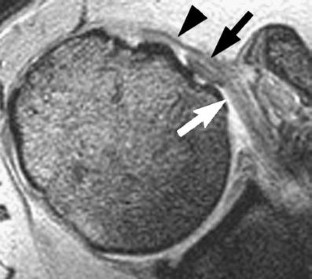

This study was reviewed and approved by our Institutional Review Board. The reports of 548 consecutive MR examinations of the shoulder were reviewed, looking for mention or description of delamination tears of the rotator cuff. The images of the identified cases were then reviewed by two radiologists to confirm the findings. Correlation with surgical and arthroscopic information was then performed. Delamination tears were defined as horizontal retraction of either the bursal or articular surface of the tendon, manifest as thickening of the torn retracted edge, and/or interstitial splitting of the tendon, manifest as fluid-like high signal intensity on fat-suppressed T2-weighted oblique coronal images.

Results

Fourteen cases of delamination tears were identified in 13 patients. Ten of the cases involved the supraspinatus tendon, all with articular surface involvement. Nine of these supraspinatus cases were isolated tears and one occurred as part of a full thickness tear. All 10 of these supraspinatus cases showed medial retraction of the articular surface of the tendon, with thickening of the retracted edge, and 5 of the 10 had a demonstrable horizontal cleft in the interstitium. Four cases involved the subscapularis tendon, with articular surface disruption in three and pure interstitial delamination in one. Medial subluxation of the tendon of the long head of the biceps was present in all four cases. No delamination tears occurred on the bursal surface. Only three of the 14 shoulders underwent surgical repair with one confirmation of supraspinatus delamination, one confirmation of a subscapularis tear that had become a full thickness tear 10 months after initial imaging and another interstitial subscapularis delamination that was not identified arthroscopically.

Delamination tears occur most often in the supraspinatus tendon, and in our series always involved the articular surface of the tendon. Only half of these tears have a visible cleavage plane in the interstitium, but this cleavage plane is not necessary for diagnosis if the torn edge is retracted.